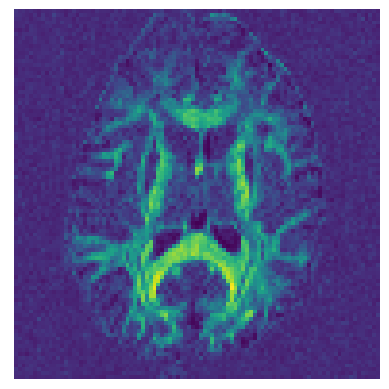

Let’s now calculate a map of Generalized Fractional Anisotropy (GFA) [2] using the DSI ODFs.

GFA = gfa(ODF)

fig_hist, ax = plt.subplots(1)

ax.set_axis_off()

ax.imshow(GFA.T)

fig_hist.savefig("dsi_gfa.png", bbox_inches="tight")